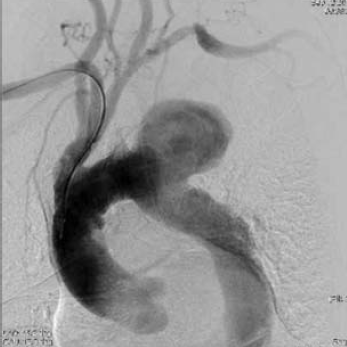

4. ábra.

PAU az aortaíven.

Az egyik szemére megvakult nőbetegnél extraperitonealis iliaca feltárás hegében hasfali sérv képződött, ami hasfali reconstructiot igényelt. A hepatitis vírushordozó nőbetegnél 18 hónappal a stentgraft beültetése után az aneurysma zsák lassú, kisfokú növekedését észleltük, benne kis kontrasztanyag halmozódással. A thrombocyta aggregatio megszüntetése után 3 hónappal nyitott intercostalis ágakból további telődést –"endoleak"- et, lassú, további expansiot igazoltunk. Ismételt CTA után döntöttünk újabb, nyitott beavatkozásról. Egy férfibeteg 90 mm átmérőjű distalis aortaív álaneuryma miatt került bal a. subclavia transpositiora, illetve stentgraft beültetésre. A beültetés során az aortaív durva mészfelrakódása ék alakú benyomatot képezett a grafton, ami ballonos tágítást tett szükségessé. A friss angiographia nem mutatott endoleaket. A sorozatos CTA ellenőrzés 8 hónappal a beültetés után az aneurysma lassú növekedését mutatta és az említett meszes carina szintjén kicsiny, II-es típusú áteresztést igazolt. A vizsgálat a graft fémvázának törését mutatta. A beteg thrombocyta aggregatio gátló kezelését megszüntettük, remélve az endoleak spontán záródását. A beteget újabb ellenőrzésre visszarendeltük, de nem jelentkezett. 3 hónap múlva a nyak bal oldalán áttört, alvadékkal elzárt sipollyal került ismét látóterünkbe, ami a friss CTA szerint a jelentősen megnövekedett, mintegy 12 cm átmérőjű álaneurysmára vezetett. Azonnal műtétre vittük, amelynek során a femorofemoralis bypass és moderalt hypothermia védelmében az endograftot eltávolítottuk, a hatalmas alvadék tömeget kiemeltük és aorto-aorticus graft interpositiot végeztük. A beteg zavartalanul gyógyult, nyaki sipolya záródott. Ismételt ellenőrzésre 5 hónap múlva panaszmentesen jelentkezett.

6. ábra.

III típusú endoleak miatt kialakult hatalmas álaneurysma az aortaíven.